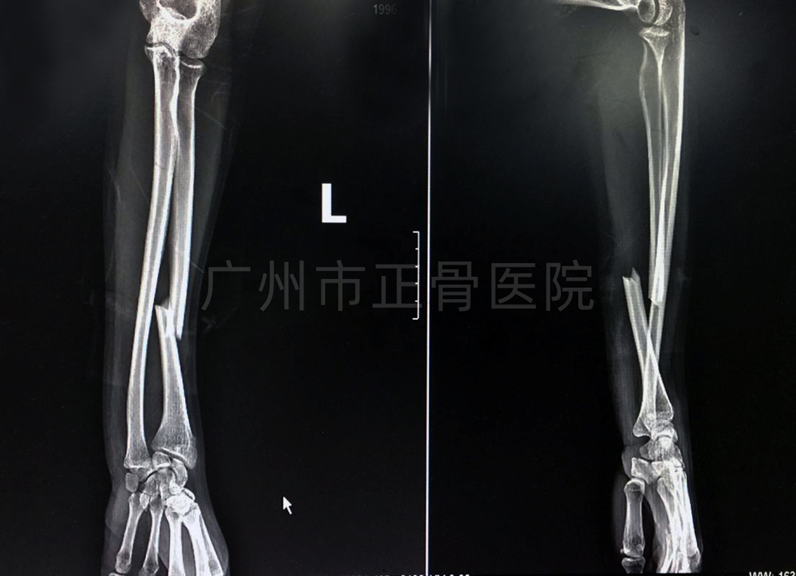

治疗:根据盖氏骨折诊疗规范,行手法复位小夹板外固定治疗。复位后复查X线片提示骨折对位对线良好。定期复诊,拍摄X线了解骨折情况,指导患者适当功能锻炼。9周后拆除外固定,指导患者加强腕关节功能康复锻炼。10周后复诊,功能基本恢复正常。

▲复位后,骨折端对位对线良好